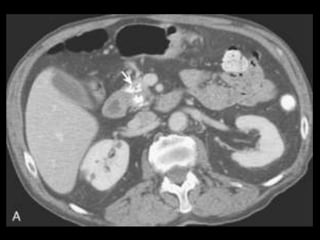

PANCREATITE AGUDA GRAVE

A administração de contraste IV é essencial,

especialmente em pacientes com PA grave, para

visualizar o pâncreas, diferenciar a glândula de

coleções líquidas adjacentes e do tecido

inflamatório peripancreático e demonstrar a

necrose pancreática.

Áreas focais ou difusas de realce diminuídas ou

ausente à TC contrastada dinâmica constituem

áreas de isquemia ou necrose.

TC tem precisão geral de 87% com S e E de 100%

para necrose extensa e 50% com áreas menores.